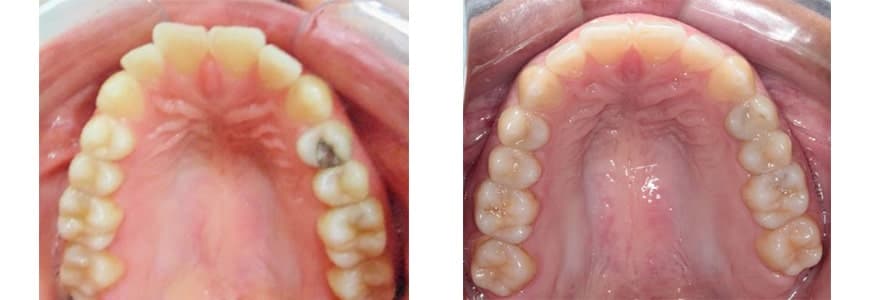

Invisalign Before & After Photos

Invisalign Fixes Crowding

10 months